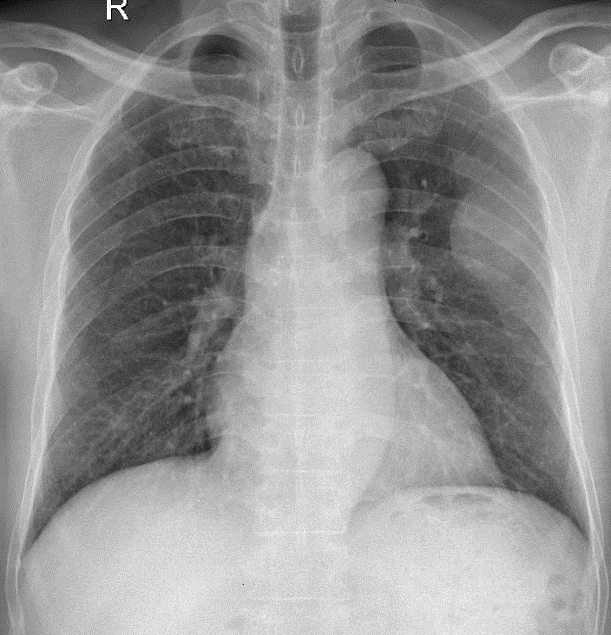

Hãy phân tích tình huống Nam 56 tuổi

1-U màng phổi (T)